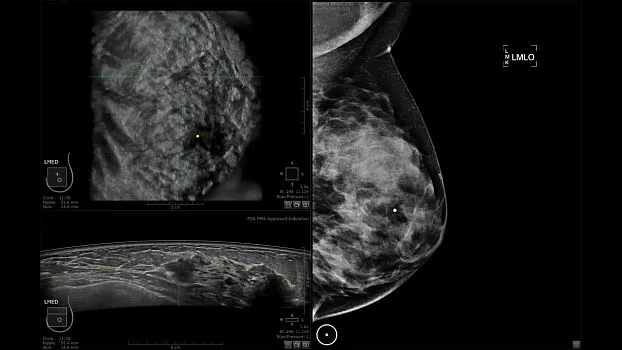

Клинические изображения

Ультразвуковая система для автоматизированного сканирования молочных желёз Invenia ABUS — это удобная, неионизирующая методика дополнительного скрининга молочных желёз у женщин с повышенной плотностью ткани. При плотной молочной железе традиционная маммография может пропустить более 1/3 раковых опухолей. Использование же Invenia ABUS в дополнение к маммографии может улучшить обнаружение инвазивного рака на 55% по сравнению с проведением только лишь одной маммографии.

• Получение объемных 3D изображений с возможностью покадрового просмотра

• Получение изображений:

• Поперечная плоскость (в реальном времени)

• Коронарная плоскость (статическая, для указания нахождения соска)

• Отображение объемных 3D ультразвуковых изображений, которые состоят из традиционных поперечных и воссозданных коронарных и сагиттальных проекций